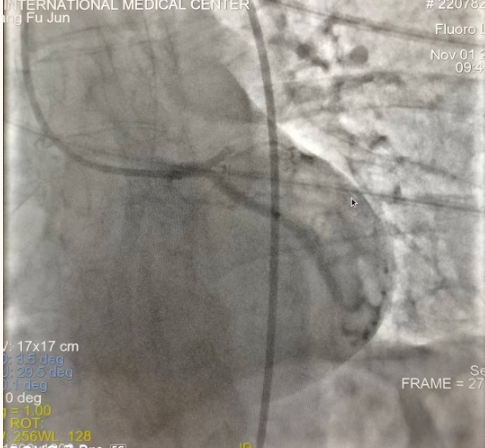

閉塞的血管再通時間取決于急救時長、轉運時長和治療時長,在前兩方面,醫(yī)院已為患者爭取了最短時間?;颊呒覍龠h在陜北,雖然已在趕來的路上,但最快抵達西安也要3小時,在與患者家屬電話溝通同意急診手術后,醫(yī)療總值班代家屬簽字,康曉軍在請示心臟病醫(yī)院王海昌院長及心臟內科CCU尚福軍主任后,積極進行術前準備。在沒有家屬陪同、沒有交費、沒有辦入院手續(xù)的情況下,患者經(jīng)胸痛中心綠色通道被送往心臟冠脈介入手術室,打通了完全閉塞的心臟前降支近段血管。